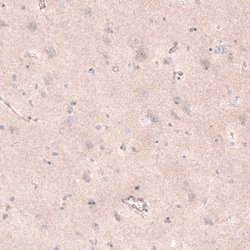

The basic helix-loop-helix transcription factor TCF21/Pod1 (also called capsulin or epicardin) is involved in kidney, lung and spleen organogenesis. It is also essential for normal development of the testes and ovaries. TCF21/Pod1 is involved in the transcriptional repression of steroidogenic factor 1 (Sf1/Nr5a1/Ad4BP), an orphan nuclear receptor that regulates the expression of multiple genes (including Scc) that mediate sexual differentiation.

| Immunohistochemistry, Western Blot | |